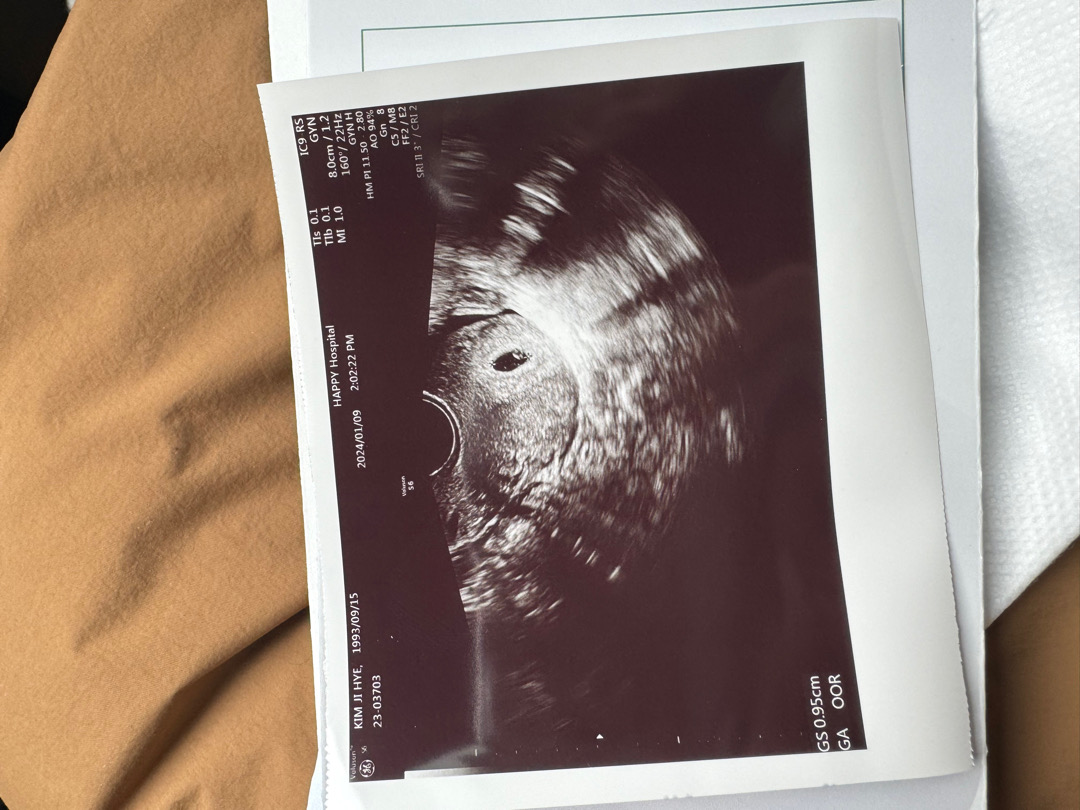

안녕하세요! 12월 7일 시작 12일 생리가 끝났어요! 병원에서 피검수치가 많이높아서 아기집 보일테니 아기집보러오라해서 어제 아기집 봤어요 아직 모르는게많아서 서툴지만 하나하나 함께 공유하고 배워나갔으면해요💖